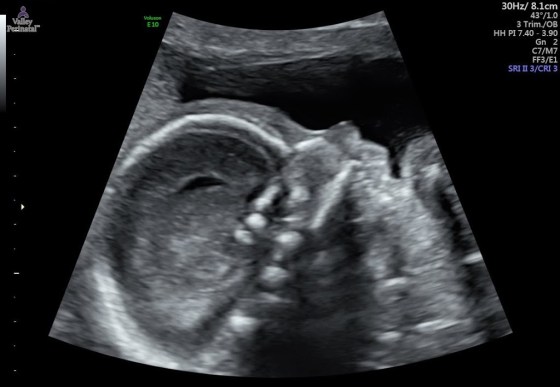

And last but not least, pictures of baby brother! Isn’t he already cute??